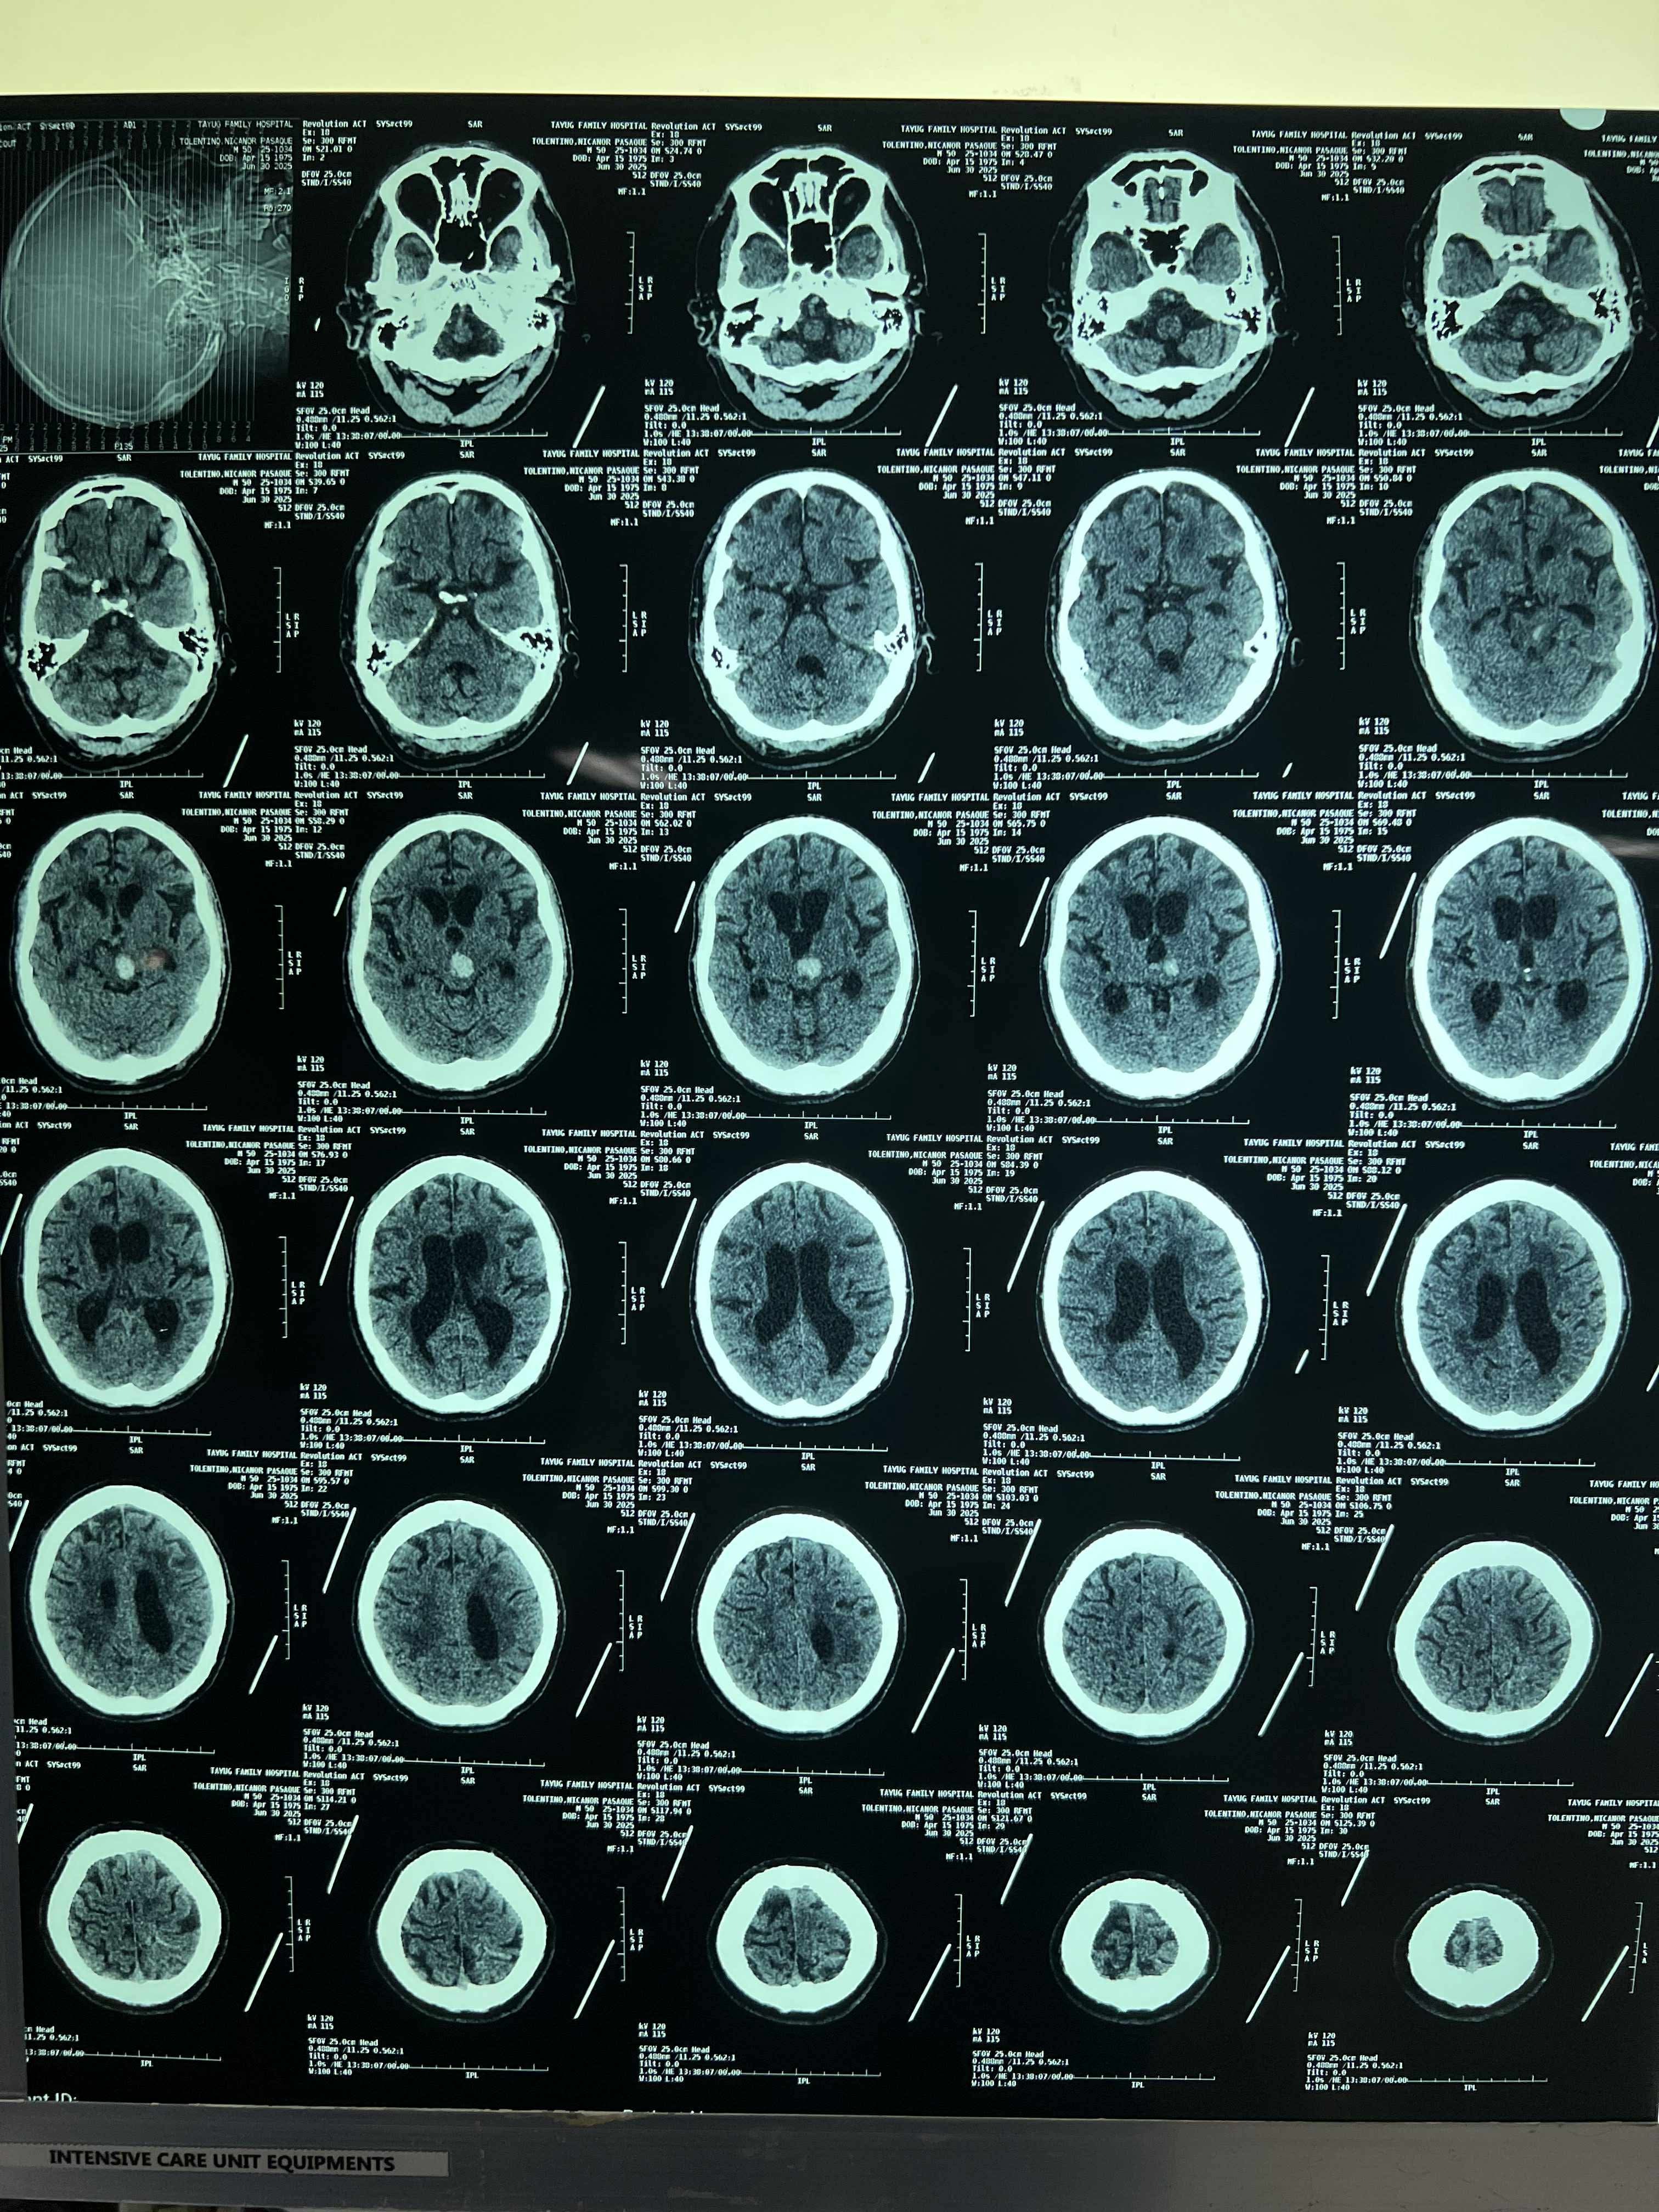

Brayan’s father recently suffered a massive stroke—his fourth—and is currently in a coma. The cost of hospital care in the Philippines is overwhelming, and the financial burden has become too heavy for Brayan to carry alone.